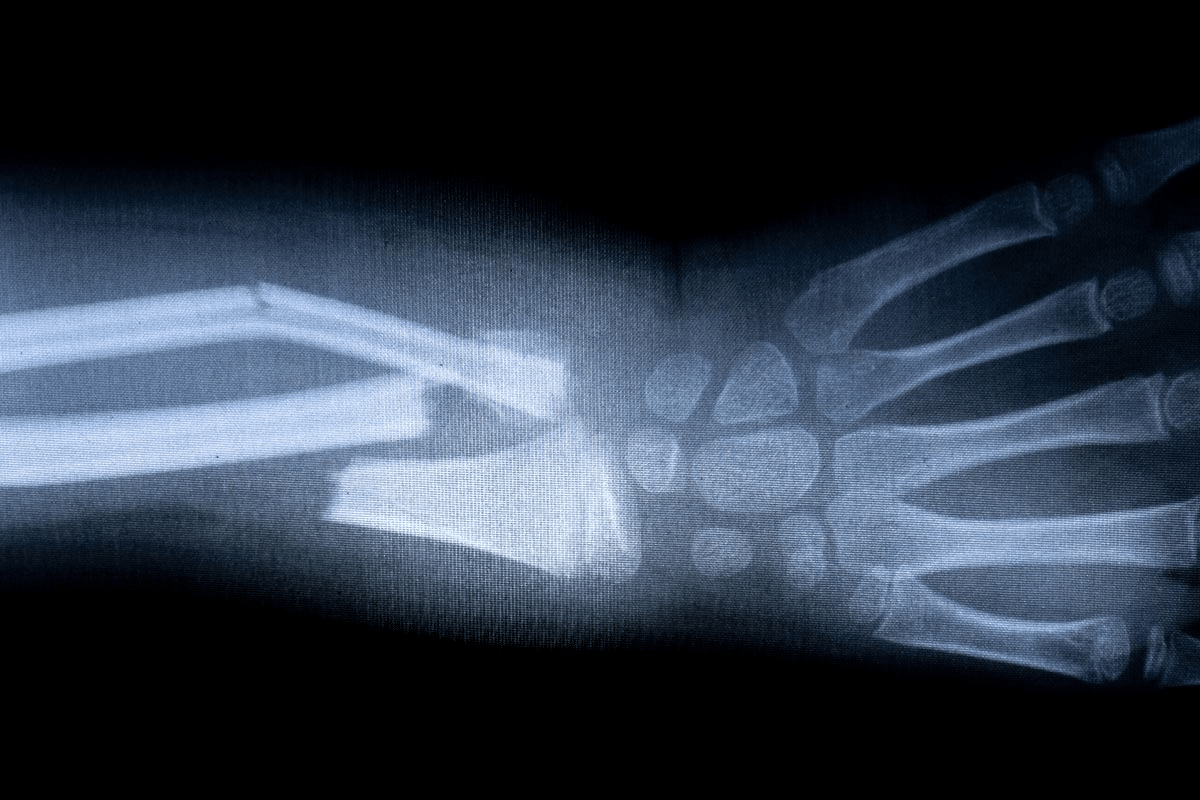

Open vs. Closed Fractures

Fractures are also classified as open or closed. An open fracture, or compound fracture, happens when the bone goes through the skin, making a wound. This is a serious emergency because of the risk of infection.

A closed fracture is when the bone breaks but doesn’t go through the skin. Closed fractures are less complicated but need quick medical care to heal right and avoid problems.

Acute traumatic events are a top fracture cause. These include falls, direct hits, or kicks, and car accidents. Such incidents apply sudden, strong force to bones, causing fractures. For example, a fall can break a wrist, and a direct hit can fracture the shin.

Diagnostic Imaging Techniques

Imaging tests help figure out if a bone is broken and how bad it is. X-rays are often the first choice because they show bone well. But, some breaks might not show up on X-rays.

CT scans or MRI are used when X-rays don’t work. CT scans help with complex breaks. MRI shows soft tissue injuries too.